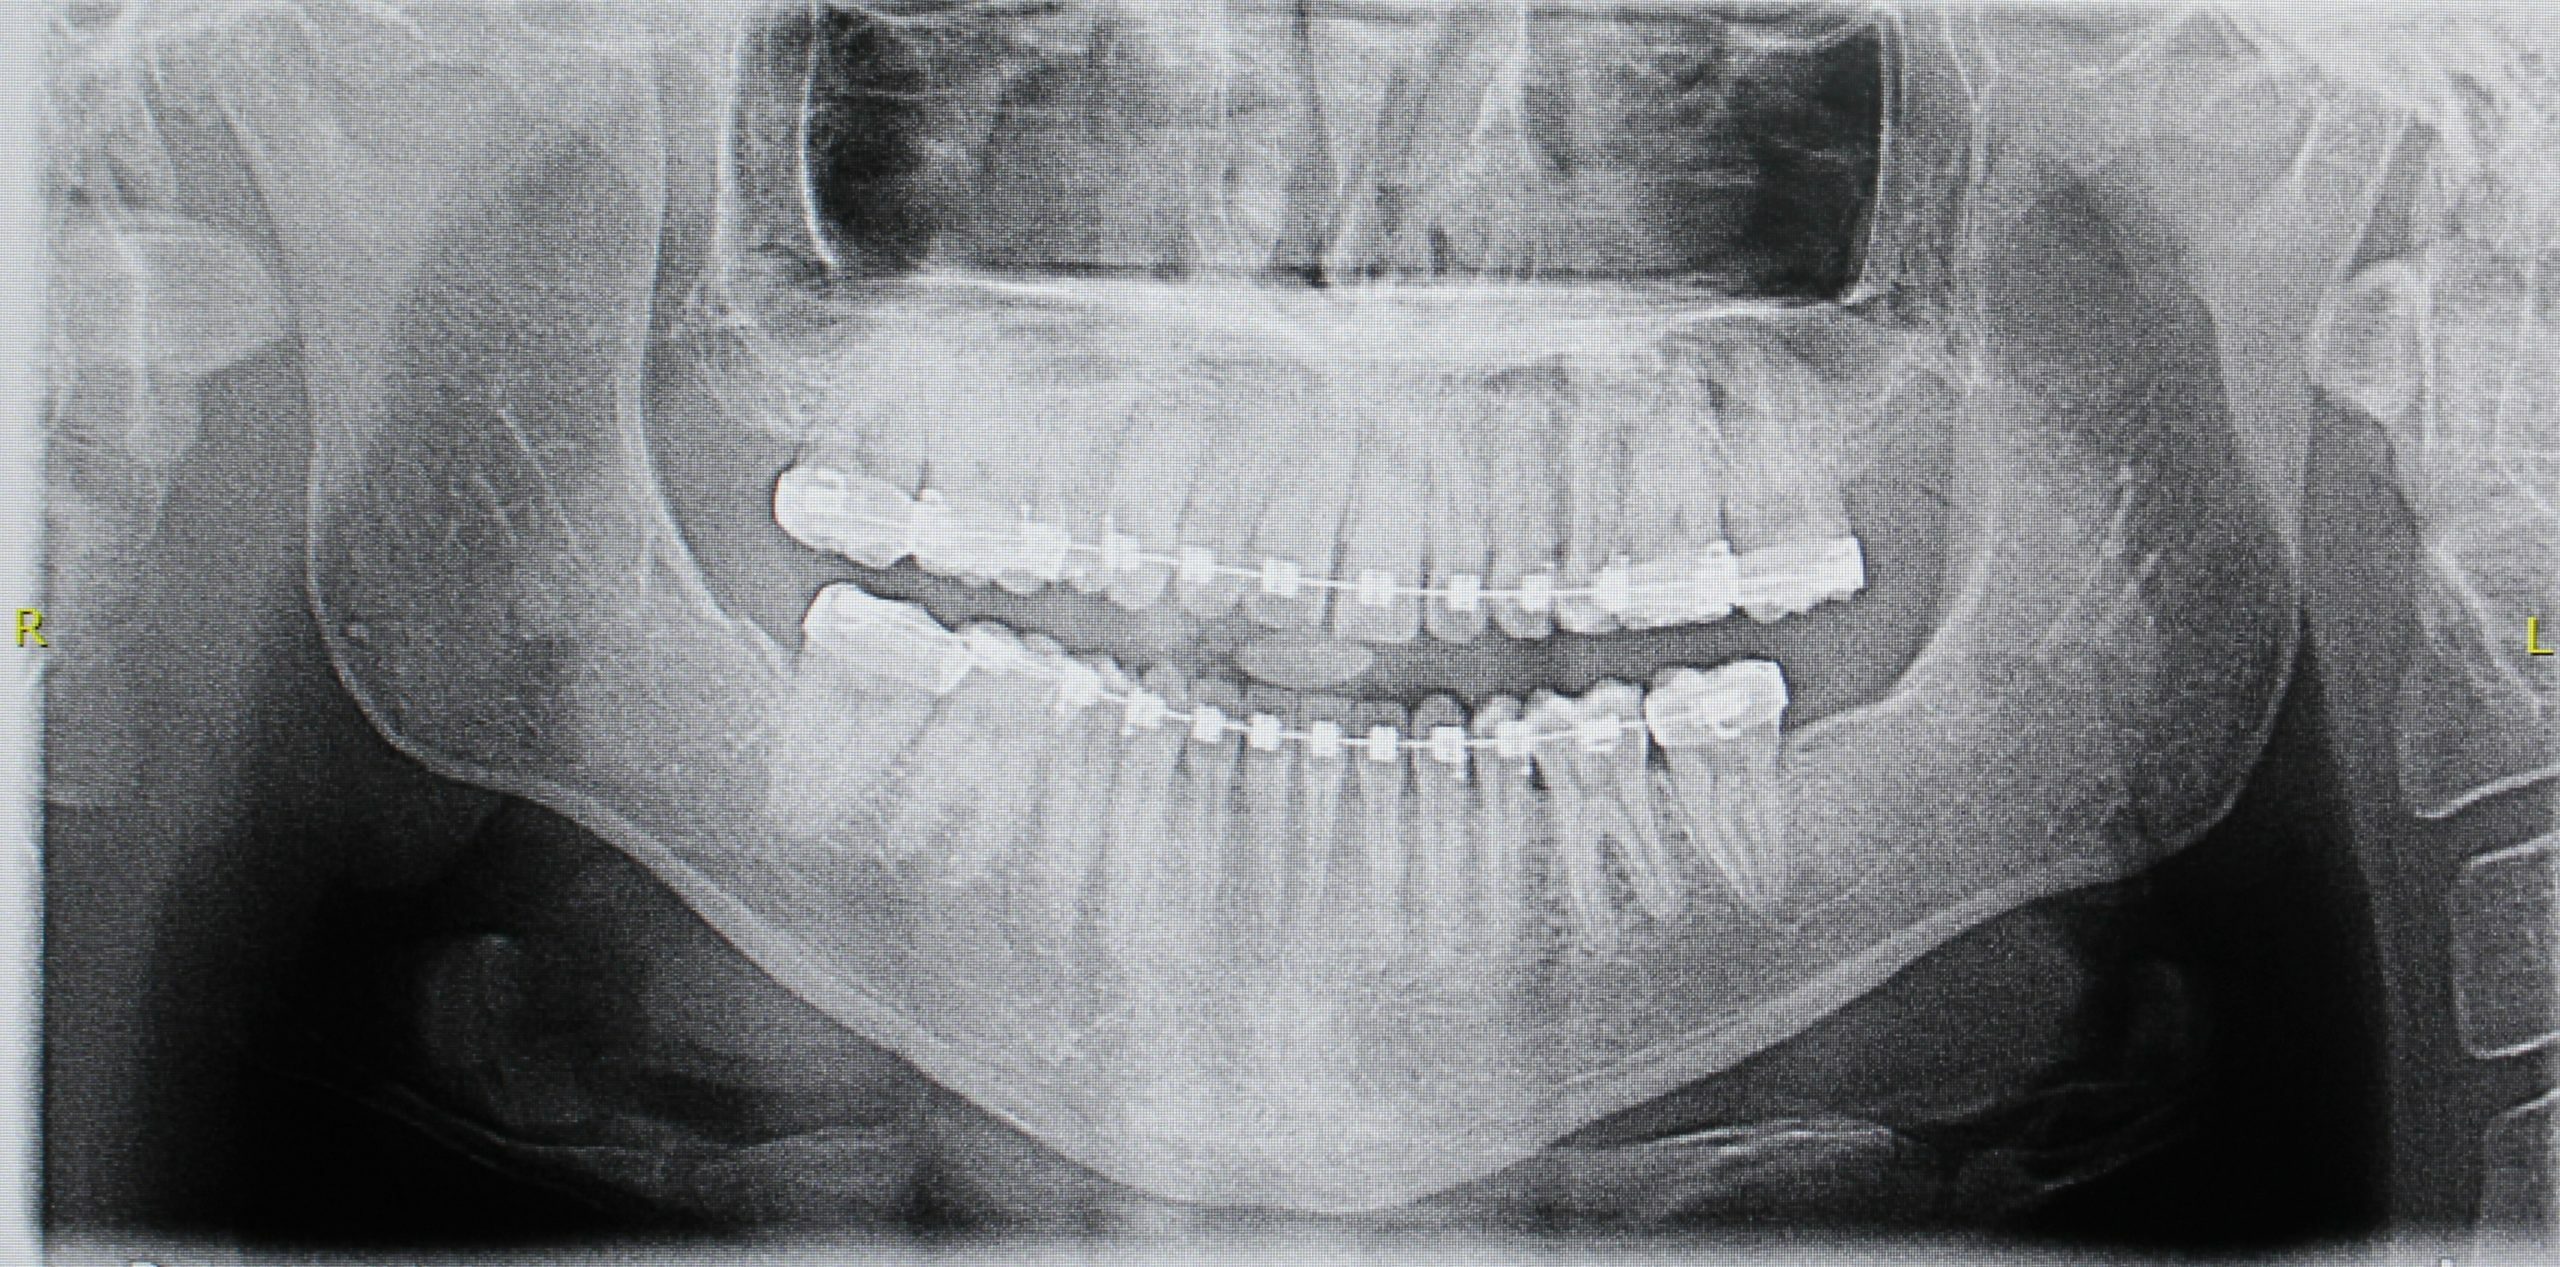

• Tratamiento Ortodóncico Previo: Esencial para alinear los dientes y garantizar que la mordida (oclusión) encaje perfectamente tras el movimiento quirúrgico.

• Intervención Quirúrgica Maxilofacial: Reposicionamiento de los maxilares a la posición ideal, definida en la planificación virtual. Esto logra Armonía Facial y Mejora Funcional. El hueso movilizado se estabiliza con miniplacas de titanio.